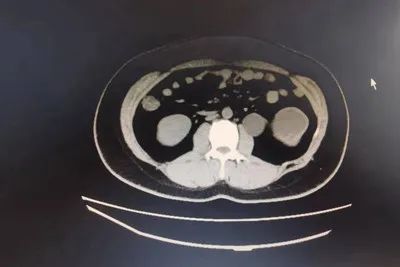

泌尿系CT及逆行造影检查,示:左肾重度积水、肾盂扩张,输尿管肾盂连接部以下无扩张积水,肾盂呈肾内型肾盂。